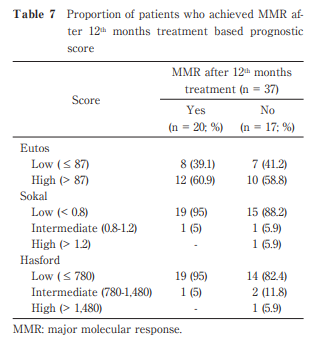

Predictive Factors of Patients with Chronic Phase Chronic Myeloid Leukemia Treated with Tyrosine Kinase Inhibitor

Ni Made Renny Anggreni Rena et al.

Published online : December 26 , 2024